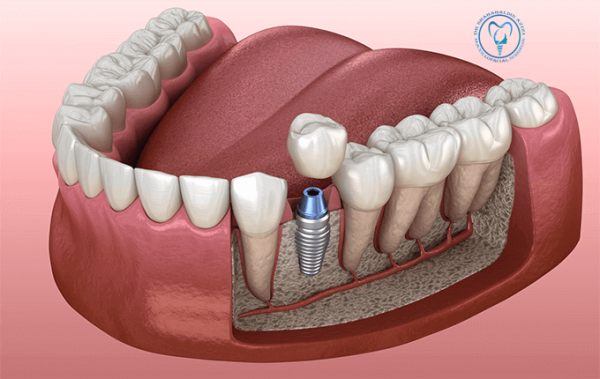

ایمپلنت طلا: راهنمای کامل، مزایا، معایب و هزینهها ایمپلنت طلا، یکی از گزینههای خاص، لوکس و بادوام در دندانپزشکی زیبایی است که هم جنبه درمانی دارد و هم میتواند نشاندهنده سبک و سلیقه فرد باشد. در این مقاله به بررسی همهجانبه این نوع ایمپلنت میپردازیم. ایمپلنت طلا چیست؟ ایمپلنت طلا نوعی جایگزین دندان است که…